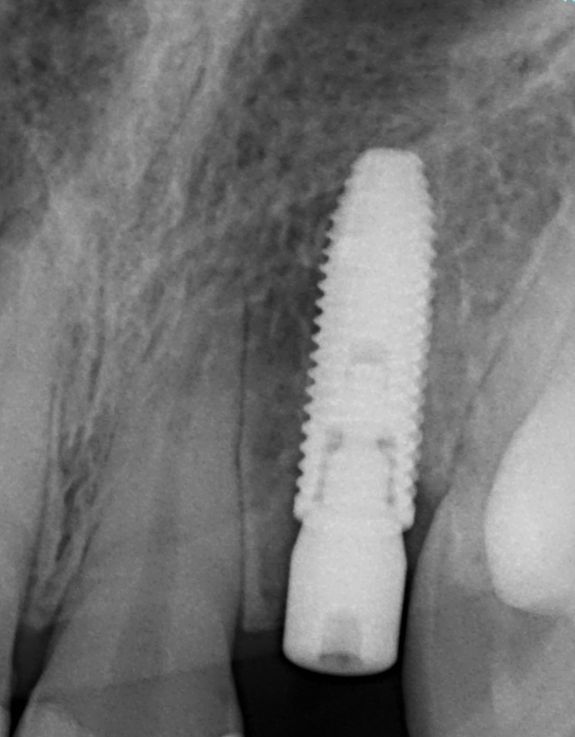

У молодой девушки после неоднократных попыток восстановления бокового резца консервативными методами произошел перелом корня. У пациентки было важное пожелание-не оставаться без зуба ни одного дня. Проведено атравматичное удаление бокового резца, одномоментная установка имплантата Nobel Parallel. Ортопедом установлена временная коронка в день операции.